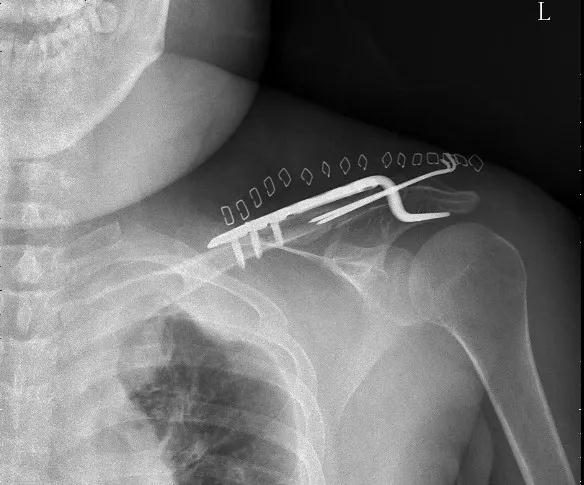

(锁骨骨折术后